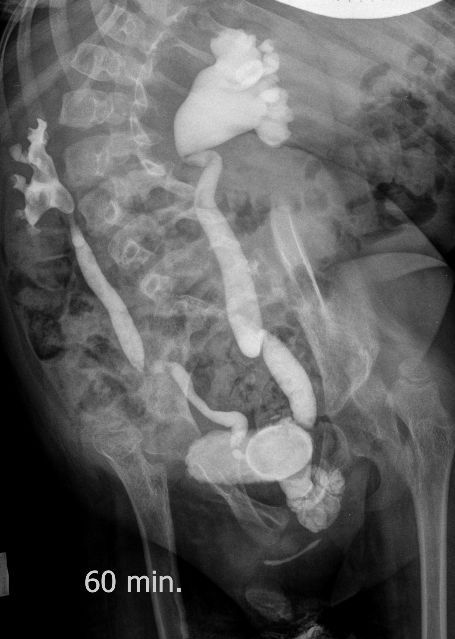

Поскольку откликов нет, добавляю экскреторные урограммы этого же пациента

И что законтрастировалось на экскреторных урограммах около мочевого пузыря?

DX0004.jpg

Если честно, и я изначально не совсем понял, где находится конкремент (а это конечно же конкремент), локализованный на урограммах. При первичном исследовании на УЗИ его я не видел (либо он спрятался за тенью конкремента мочевого пузыря, либо я обрадовался редкой находке конкремента такого размера в мочевом пузыре - 2.5 см, и не посмотрел что ниже). Тем не менее при ретроспективном анализе архивированных сонограмм, как мне кажется, он попал в один из сканов, м.б. не совсем чётко.

И всё -же, где конкремент :?:

Возможно, в дивертикуле либо в нижней трети мочеточника..

Верификация:

Выдержка из протокола операции- "...вскрыт мочевой пузырь, обнаружен камень 4 х 3х 2.5 см, плотный, удалён. При дальнейшей ревизии мочевого пузыря обнаружен вколоченный камень в шейке мочевого пузыря и в уретре, удалён камень 2 х 1.5 х 1.5 см. При осмотре устья левого мочеточника - последний зияет, мочеточник расширен до 1 см, учитывая расширение мочеточника, проведена антирефлюксная пластика по Грегуару..."

На экскреторной урограмме - размеры собирательной системы левой почки уменьшились. Визуализирована расшиенная контрастированная проксимальная уретра.